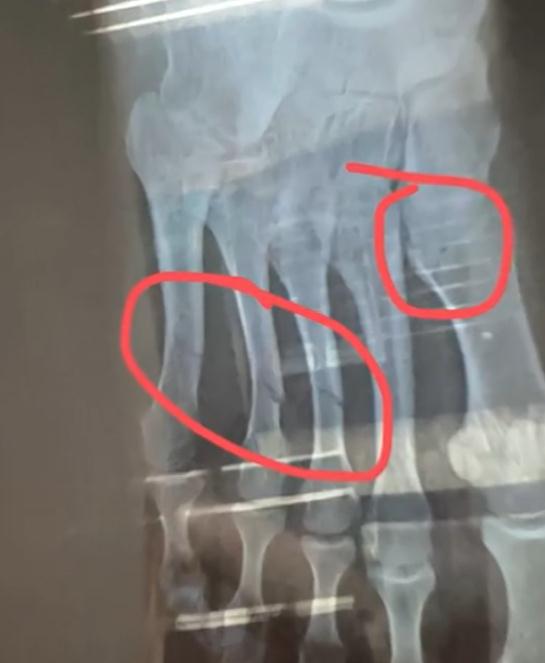

健身房工作人员梁教练称,当时视频中的白衣男生正在单侧卸片,致使健身器械失衡侧翻,砸中一旁的女生。女孩被砸中了脖子胸和腰部等位置,随后被送去就医。在经过CT等全身检查后,发现她脚趾断了4根。